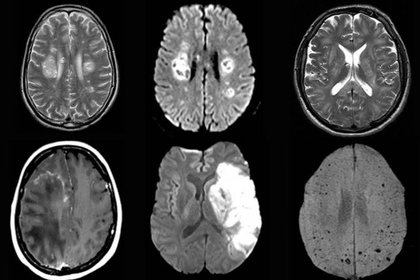

Hallazgos incidentales en la resonancia magnética cerebral de niños

El 25% de los estudios realizados en niños asintomáticos mostró al menos una anomalía, pero sólo el 0,4% requirió seguimiento clínico. Debe tenerse en cuenta la alta frecuencia de hallazgos incidentales en la interpretación de estos estudios. New England Journal of Medicine, 19 de octubre de 2017